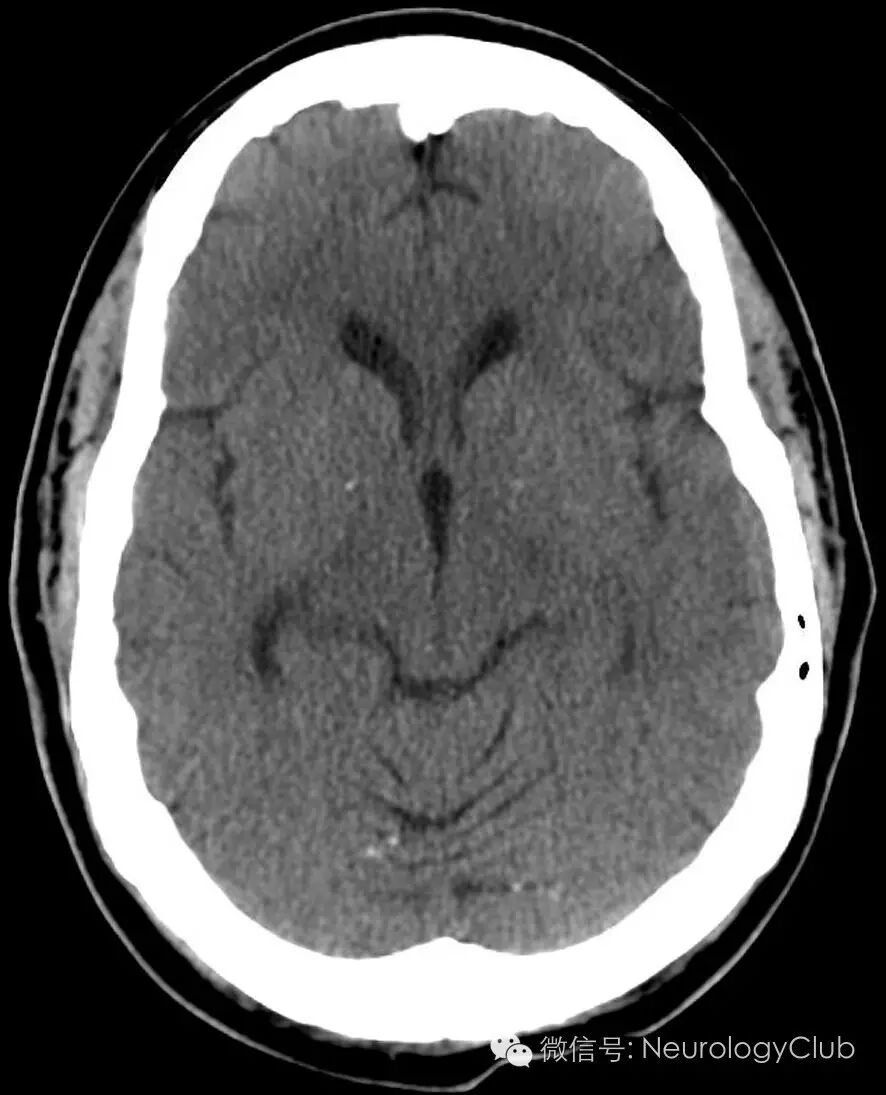

48岁女性,既往有高血压,糖尿病,高脂血症,近期髓系白血病急性变行尼洛替尼化疗,本次表现为意识状态改变,左上肢无力,恶心呕吐,推测可能为卒中。大约12小时前,患者完全正常。查体提示患者思睡,对自身病史不能很好回忆。时间,姓名回答正确,能遵嘱动作。存在构音障碍。右侧肢体肌力5级,左侧肢体2级伴左侧面瘫。CT提示右侧额颞叶高密度,像出血的卵圆形肿块(图1)。MRI证实右侧大脑凸面4.7×2.7cm附着于硬脑膜的强化病灶(图2)。

(图1:横断面CT提示右侧额颞叶一较大的高密度的卵圆形肿块伴血管源性水肿和中线移位)